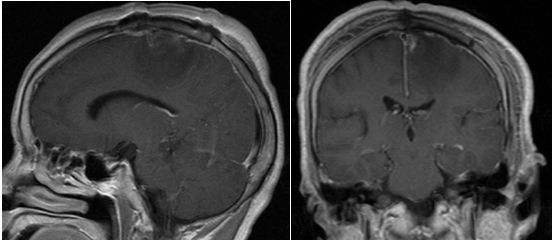

图3. 术后复查头颅磁共振,示肿瘤全切。

术后患者神志清,对答切题;复查MRI示肿瘤全切。至术后一周出院时右下肢肢体肌力4+级,活动可以控制,余无阳性体征发现。